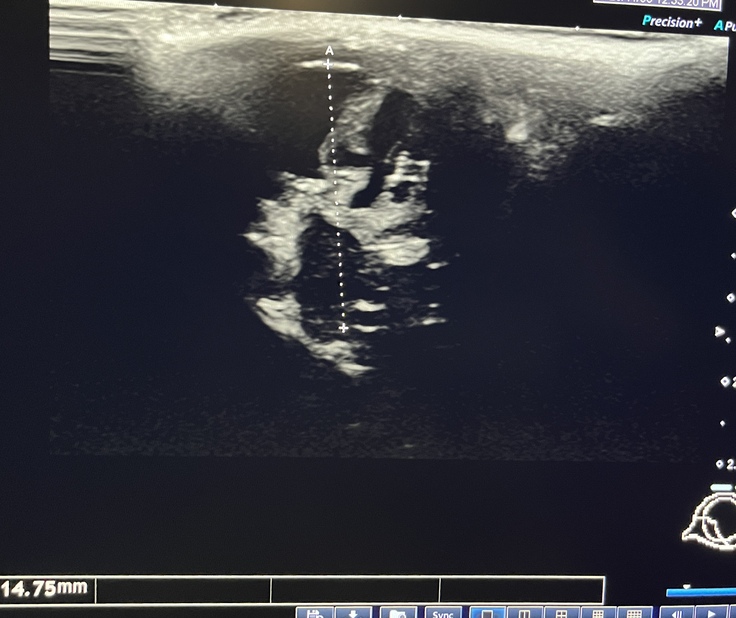

↓検査の様子。エコー写真は目を上から見た図です。損傷した左眼の眼球ろう萎縮が、緊急手術直後11mm→現在14.7mmまで戻ってきております。しかし中の組織は正常な右目と比べると損傷が激しく元には戻らず、一部白内障となっております。

↓一方の正常な右目は 直径18.22mmあり、中の組織も綺麗です。